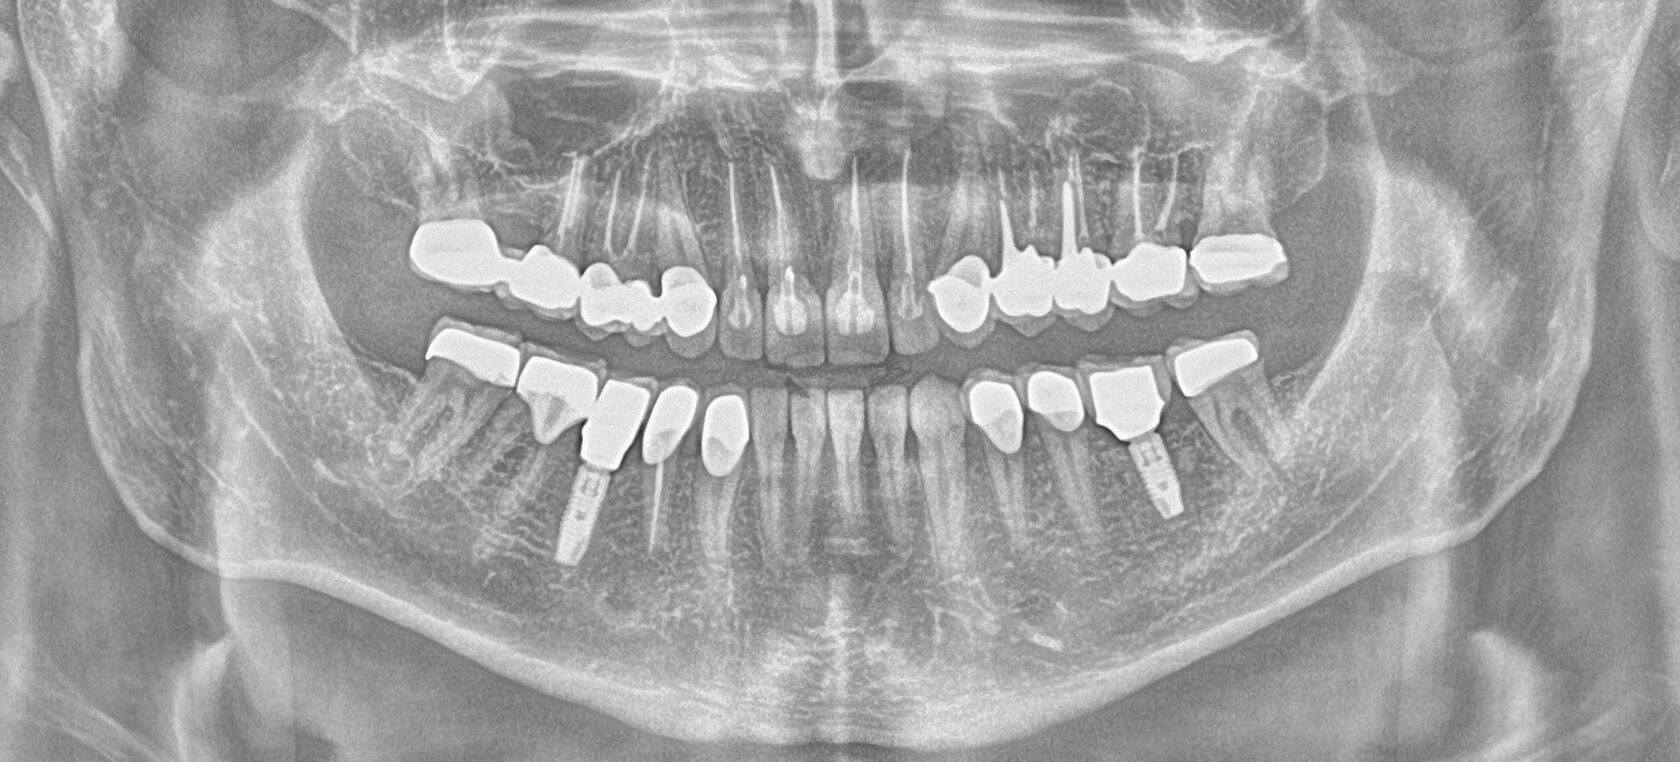

В данном клиническом случае представлена комплексная работа, состоящая из:

1 Терапевтический этап - лечение кариеса, подготовка корневых каналов и восстановление

культей зубов для установки коронок.

2 Хирургчий этап - удаление 2-х зубов с одномоментной дентальной имплантацией.

3 Сложное функционально-эстетическое протезирование (завышение прикуса на временных

коронках, стабилизация мышечного тонуса и позиции ВНЧС, перевод временных конструкций

в постоянные).

Длительность лечения составила более 1 год.